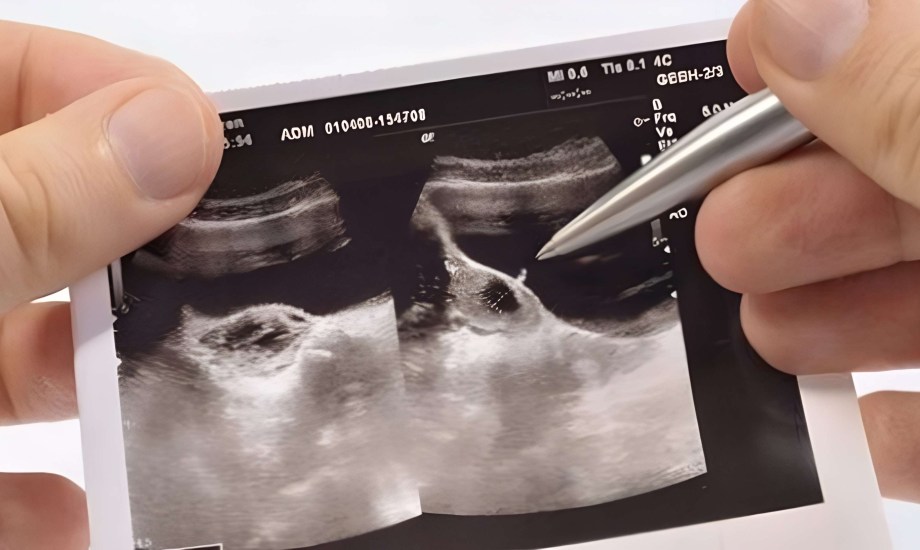

كيس الحمل الفارغ.. الأسباب والأعراض وطرق الوقاية والتعافي

تحلم المرأة بالإنجاب ولكن توجد بعض المشاكل الصحية التي يمكن أن تعرقل هذا الحلم بما في ذلك كيس الحمل الفارغ، الذي يمكن أن يزيد من فرص الإصابة بالإجهاض، وبناءً على ذلك، ينبغي أن تكون الأم على دراية بما يمكن أن تمر به خلال فترة حملها.

بالنسبة لبعض السيدات، يمكن أن يحدث الإجهاض في غضون أيام قليلة من نتيجة اختبار الحمل الإيجابي، وبالوقت نفسه، تعتقد بعض الأمهات أنهن حوامل، وفي هذه الحالة، يعرفن في أول لقاء مع الطبيب أنهن يعانين من كيس الحمل الفارغ.